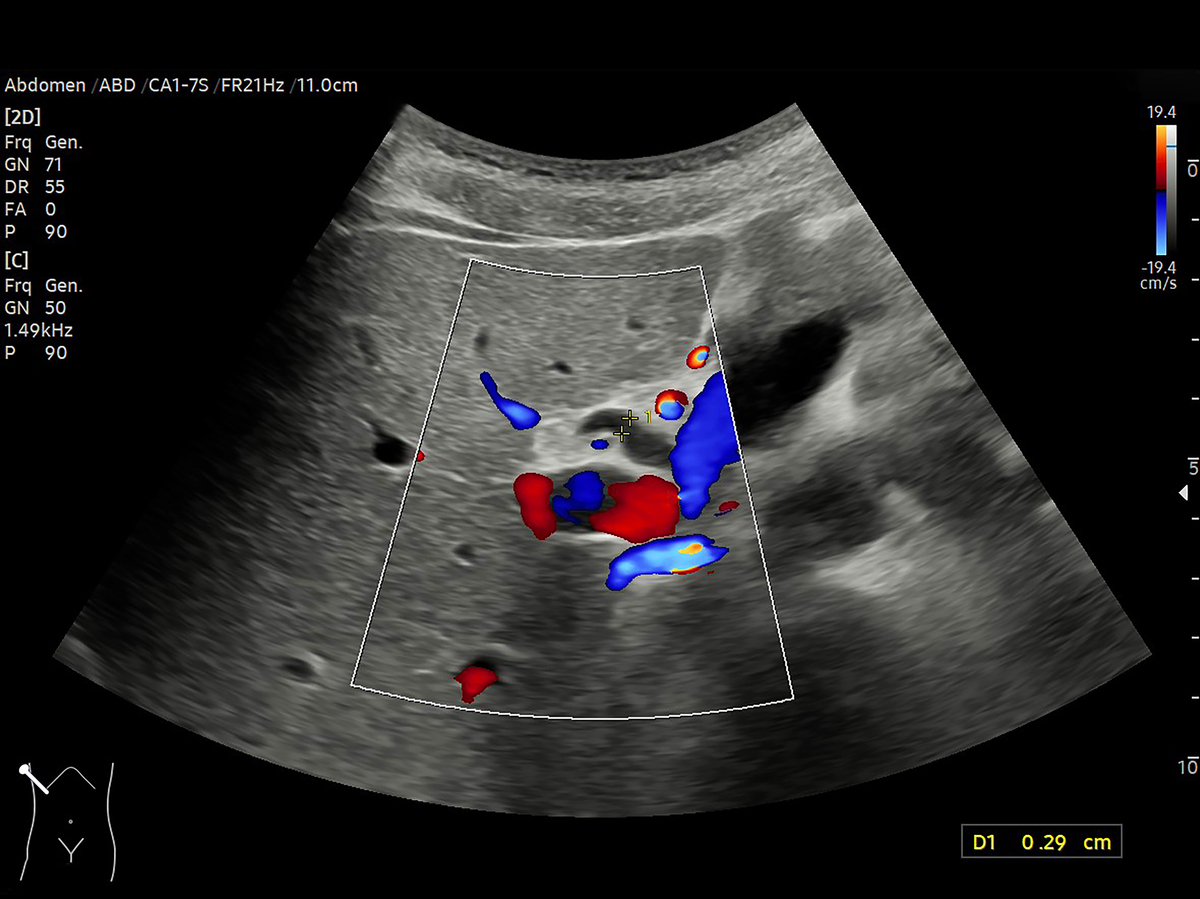

4. 血流变化:子宫内膜增生症患者的子宫内膜血流通常会增加,血流速度也会加快。

子宫内膜增生:经腹部超声检查特征